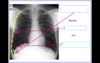

Q

Identify

A

Identify

Q